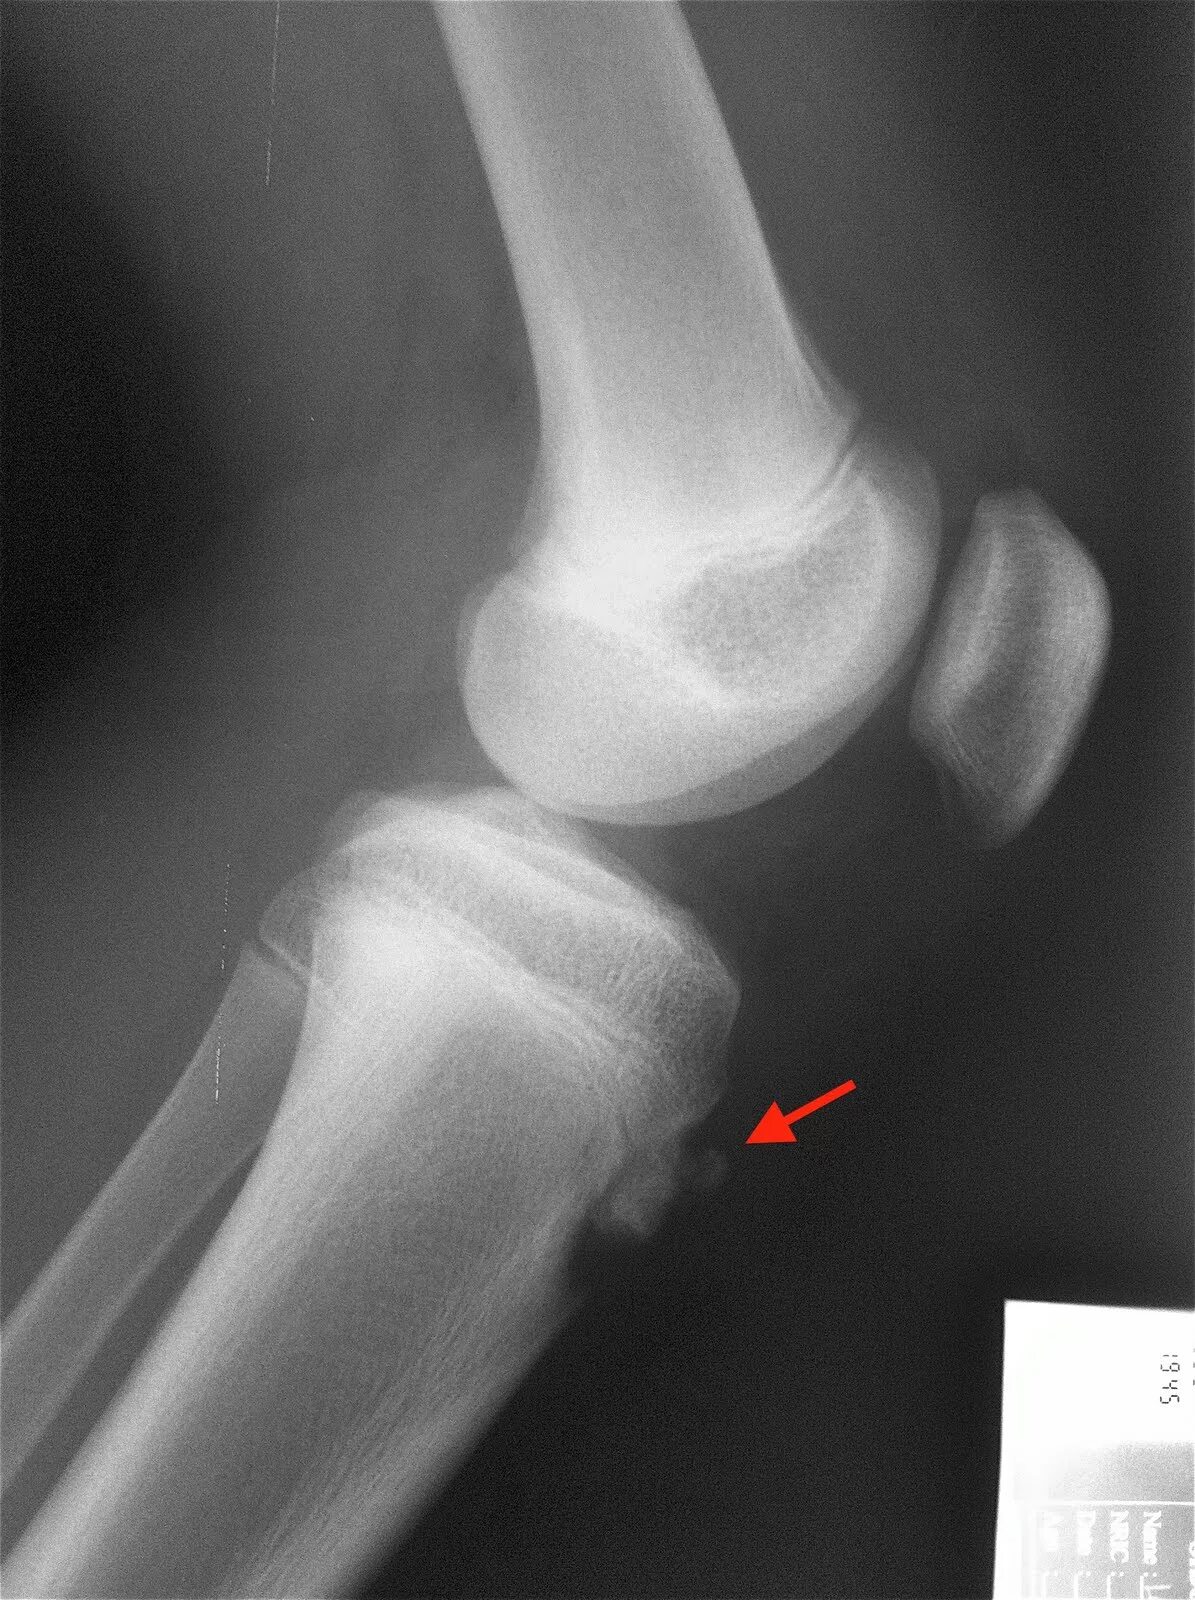

Синдром осгуда шляттера